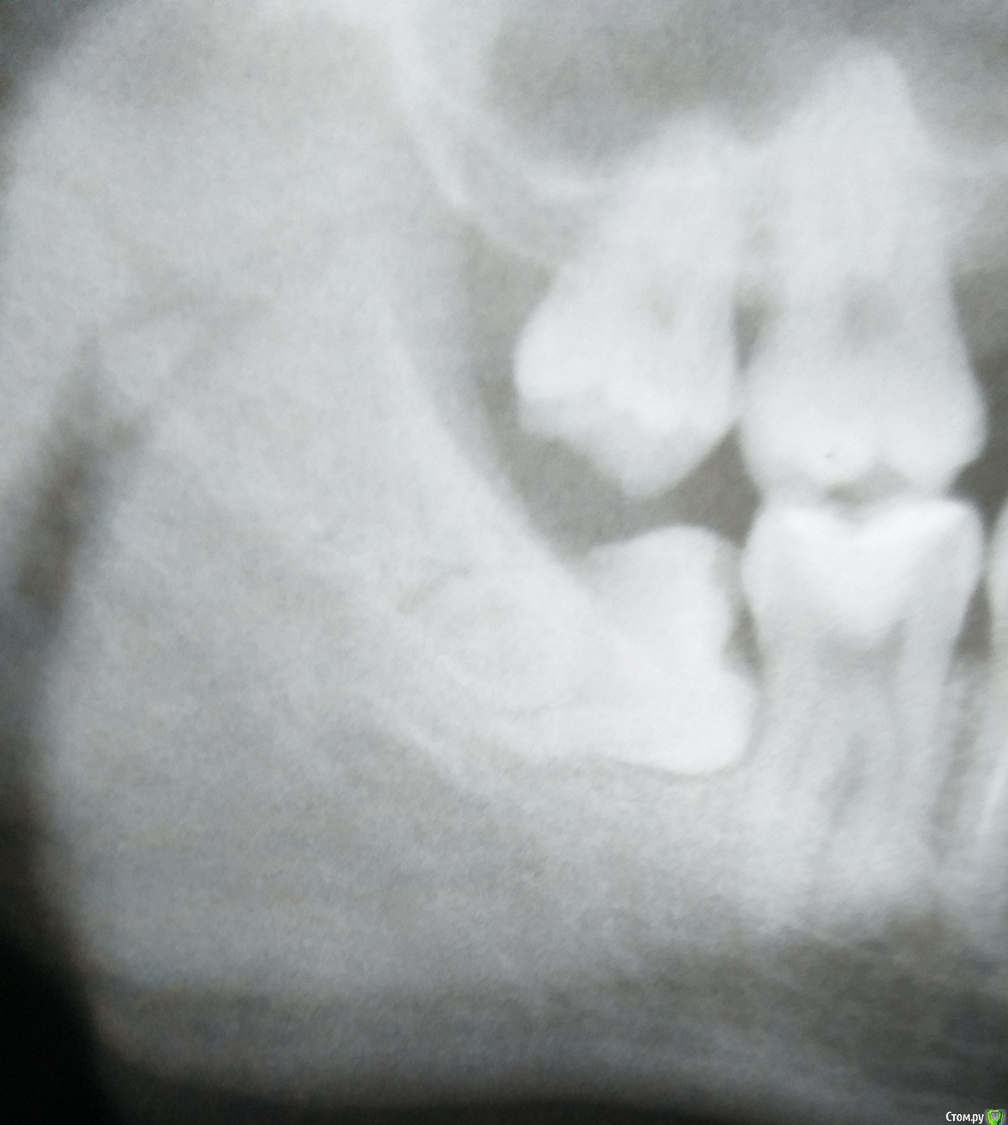

abc32 Опубликовано 5 февраля, 2021 Поделиться Опубликовано 5 февраля, 2021 Здравствуйте.Планирую удаление нижней правой 8ки, которая лежит на боку, на четверть примерно выглядывает из десны и упирается в соседнюю 7ку. Надеюсь, что прикрепленное фото видно.Еще пару лет назад несколько хирургов и ортодонт на консультации говорили, что эту 8ку лучше удалять, т.к. она может двигаться, может быть повреждение ближе к корню соседней 7ки из-за попадающей туда пищи, и в итоге придется удалять оба зуба. Проблемы с застреванием пищи есть, постоянно приходится зубочисткой пользоваться, на ночь промываю область ирригатором, периодически появляются продолжительные неприятные ноющие ощущения между зубами, но не часто, может раз в 3 недели на полдня.На днях моя мать обращалась к хирургу с удалением своего зуба (гос.поликлиника), попросил заодно показать ей с телефона снимок моего зуба, спросить что нужно для плановой записи. Врач ей ответила, что если не беспокоит зуб, то лучше не трогать, т.к. либо придется 7ку тоже удалять, либо сзади кость подрезать, а может и вообще в челюстно-лицевую направлять на удаление. Вариант с удалением 7ки меня очень удивил, т.к. до этого ни один врач об этом ни слова не говорил, этот вариант, само собой, не подходит. Совсем не трогать тоже сомнительный вариант, т.к. и неприятные ощущения в области соприкосновения беспокоят, что может однажды все равно придется удалять, но уже оба.До этого полтора года назад на лечении других зубов у терапевта поинтересовался какого он врача может посоветовать для удаления 8ки. Он сказал, что есть одна женщина в частной клинике, специализируется как раз на удалении 8к, делает это аккуратно, по частям, по кусочкам, и что так даже лучше, потому что грубая мужская сила может наоборот навредить, т.к. случай непростой. Но стоимость удаления у нее от 10 тысяч рублей (по ценам почти двухлетней давности, г.Брянск), а я и так уже прилично потратился на две имплантации в последний год, дополнительных трат не хотелось бы. Но "оптимизм" врача в гос.поликлинике немного пугает =)Вопросы, которые меня беспокоят:1. На сколько может быть проблемным данный зуб при удалении? Может лучше его не трогать? Но очень я устал за несколько лет постоянно прочищать данную область между зубами, тем более появляются иногда болезненные ощущения.2. Может действительно не жалеть денег и пойти в платную клинику, чтобы не нарваться на работу "спустя рукава" врача в городской?3. Стоит ли вообще заморачиваться с этим советом по поводу того, что женщина-врач аккуратнее сделает удаление?) До этой 8ки удалял две другие у врача-мужчины в той же гос.клинике, прошло всё хорошо, я доволен, но и случаи там были проще.Очень надеюсь, что подскажите, как лучше поступить. Спасибо Ссылка на комментарий